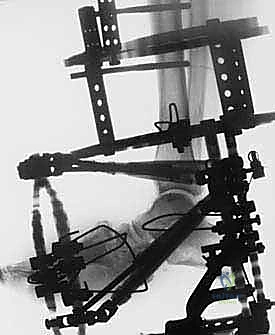

لتجاوز كل العيوب القاتلة للجراحات التقليدية، يبرز تفوق طريقة التصحيح التدريجي على مرحلتين التي يتقنها ويطبقها الأستاذ الدكتور محمد هطيف ببراعة منقطعة النظير. هذه الطريقة تعتمد على مبادئ الميكانيكا الحيوية المتقدمة (استخدام جهاز إليزاروف أو إطارات تايلور المكانية السداسية الأبعاد - Taylor Spatial Frame).

تسمح هذه التقنية بإعادة محاذاة دقيقة ومتحكم بها (مليمتر بمليمتر) للمفاصل المخلوعة أو المتفككة في قدم شاركو. من خلال التشتيت التدريجي (Gradual Distraction)، يتم شد الأنسجة الرخوة والأوعية الدموية والأعصاب ببطء شديد، مما يمنحها الوقت للتكيف والنمو دون أن تنقطع أو تتلف.

2. المرحلة الأولى: تطبيق جهاز التثبيت الخارجي (External Fixator Application)

- التدخل المحدود: بدلاً من شق القدم بالكامل، يتم عمل ثقوب صغيرة جداً (بضعة مليمترات) في الجلد.

- إدخال الأسلاك: يتم تمرير أسلاك معدنية رفيعة جداً وقوية (K-wires) ومسامير نصفية (Half-pins) عبر العظام في الساق والقدم بأماكن استراتيجية محددة مسبقاً بدقة لتجنب الأعصاب والأوعية الدموية، وذلك تحت توجيه الأشعة السينية المباشرة (C-arm) في غرفة العمليات.

- تجميع الإطار: يتم توصيل هذه الأسلاك بحلقات خارجية معدنية أو كربونية تحيط بالساق والقدم (إطار إليزاروف). يتم تثبيت هذه الحلقات معاً بواسطة دعامات قابلة للتعديل.

4. المرحلة الثانية: دمج المفاصل (Joint Arthrodesis)

بمجرد أن تصبح العظام في الوضع الصحيح بفضل التثبيت الخارجي، ننتقل إلى مرحلة التثبيت الدائم.

* من خلال شقوق جراحية صغيرة جداً (Minimally Invasive)، يقوم الدكتور هطيف بإزالة الغضاريف التالفة من المفاصل المستهدفة (غالباً مفاصل منتصف القدم والكاحل).

* يتم استخدام تقنيات متقدمة لتحفيز العظام على الاندماج (مثل استخدام طعوم عظمية أو بروتينات محفزة لنمو العظم).

* يتم ضغط العظام معاً باستخدام جهاز التثبيت الخارجي نفسه لضمان التحامها كعظمة واحدة صلبة.